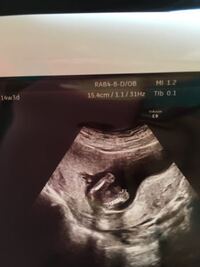

14w3d性別 男の子っぽいでしょうか まだ14週なので先 Yahoo 知恵袋